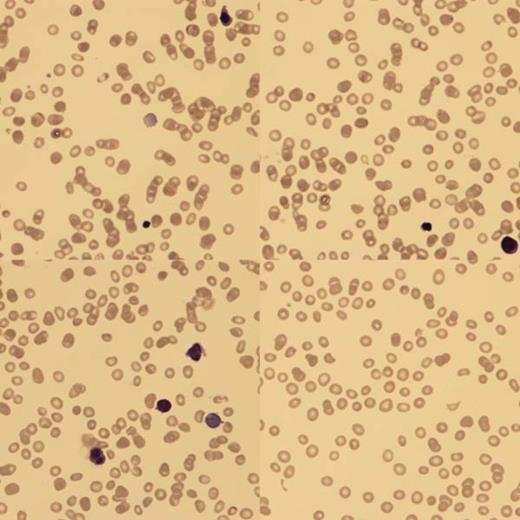

At birth, blood analysis showed Hb 4g/dl, hepatitis with conjugated hyperbilirunemia (ALT 138, AST 1603, ALP 690 and bilirubin 324). Blood film (BF) confirmed a low reticulocyte count (RETC) and nucleated red blood cells (NRBC). There was no fragmentation and the Coomb's test was negative. An ultrasound scan showed smooth hepatomegaly. Upon transfer to us, she continued to have conjugated hyperbilirubinemia and low RETC.

BF showed poikilocytes, teardrops, macrocytes and NRBC with binucleate forms.